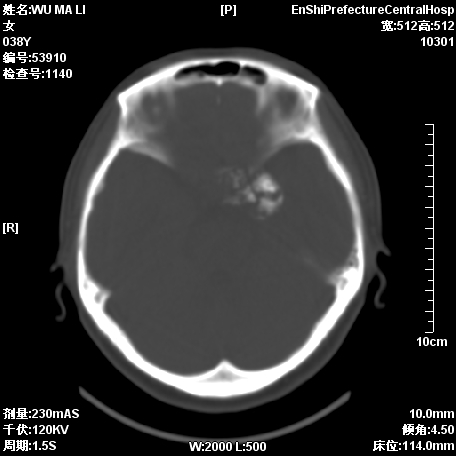

标题: CT11244:颅底病变,请教高手,已行MRI检查,随后发 [打印本页]

患者,38岁,因左侧偏盲月余求治.

补充图片

脊索瘤?脑膜瘤?

图像不全啊,考虑脊索瘤可能性大.

考虑脊索瘤可能性大

考虑脊索瘤可能性

可考虑  脑膜瘤、脊索瘤、软骨瘤

支持脊索瘤诊断

脑膜瘤?脊索瘤?

考虑为:1)脊索瘤。2)软骨瘤?

支持脊索瘤

图像不全,考虑脊索瘤可能性大.

支持考虑:  脑膜瘤、脊索瘤、软骨瘤  。